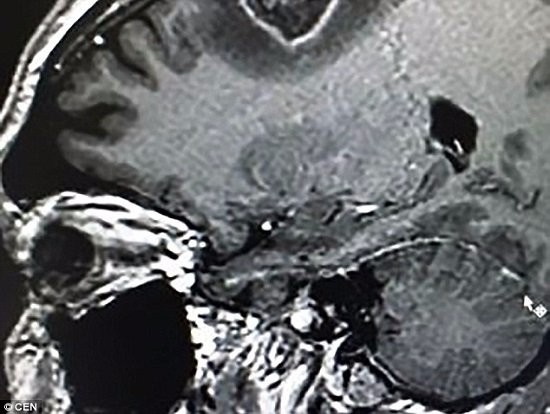

وأظهر المسح بالأشعة السينية أن لديه ورما فى الدماغ على شكل قلب، لذلك اضطررت إلى الخضوع لعملية جراحية، وكانت هناك طريقتان، وهما: التخدير الكامل، أو الاستيقاظ أثناء الجراحة .